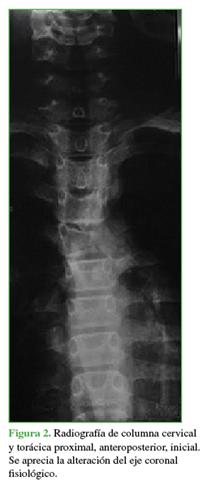

En la radiografía inicial de frente, se observó una alteración en el eje coronal fisiológico (Figura 2).

Los estudios complementarios mostraron un compromiso vertebral extenso: en C7 (arco posterior), zonas 4-7 y niveles III y IV de la clasificación de Weinstein-Boriani-Biagini; en T1 (cuerpo vertebral), zonas 10-3 y niveles III y IV; en T2 (pedículo derecho más arco posterior), zonas 3-7, niveles III y IV.11 Las lesiones eran de tipo quística expansiva (Figuras 3 y 4). Ante el patrón expansivo de la lesión, se descartó la sospecha de un hemangioma vertebral. Se interpretó el caso como una lesión con diagnóstico presuntivo de QOA grado 3 de Enneking.